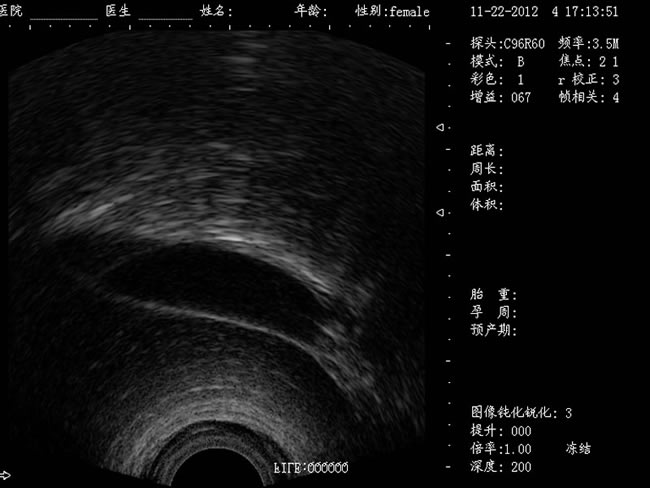

DW-400 全數(shù)字可視人流機(jī)

• 功能特點(diǎn): 定位精確 手術(shù)效率高:實(shí)時(shí)動(dòng)態(tài)頻率掃描等全數(shù)字超聲成像技術(shù)、生成精確的圖像引導(dǎo)手術(shù)器械迅速到大手術(shù)位置,避免損傷子宮內(nèi)膜和子宮穿孔的現(xiàn)象,即減輕了患者的痛苦又極大提高了手術(shù)效率。 高密度全數(shù)字波束形成:采用全新一代混頻技術(shù)、數(shù)字嵌入系統(tǒng)及數(shù)字整序技術(shù) 有效提升系統(tǒng)的穩(wěn)定性、可靠性:實(shí)時(shí)動(dòng)態(tài)孔徑成像,充分保證圖像的精度和清晰度。

定位精確 手術(shù)效率高:實(shí)時(shí)動(dòng)態(tài)頻率掃描等全數(shù)字超聲成像技術(shù)、生成精確的圖像引導(dǎo)手術(shù)器械迅速到大手術(shù)位置,避免損傷子宮內(nèi)膜和子宮穿孔的現(xiàn)象,即減輕了患者的痛苦又極大提高了手術(shù)效率。

有效提升系統(tǒng)的穩(wěn)定性、可靠性:實(shí)時(shí)動(dòng)態(tài)孔徑成像,充分保證圖像的精度和清晰度

a) CXA10R 腔內(nèi)探頭:152º可視可調(diào);